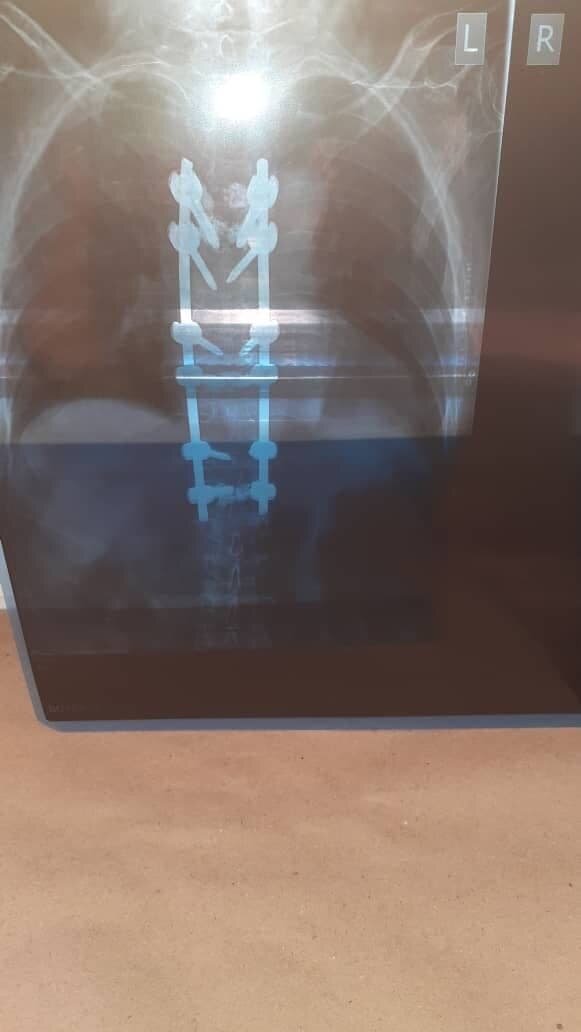

Технологии здоровья

На лечение пациентка легла в НИИ травматологии и ортопедии имени Вредена, а операцию проводил известный хирург, профессор Дмитрий Пташников. Операция была сложной, доктор этого не скрывал, но все прошло удачно. Пациентке выполнили спондилосинтез с фиксацией винтов на цемент и вертебропластику позвонков костным цементом. Позже женщина призналась, что очень переживала и боялась после вмешательства остаться прикованной к инвалидному креслу. Но врачи успокоили: в Петербурге операции на позвоночнике и спинном мозге проходят с использованием интраоперационного нейромониторинга. Аппарат отслеживает нервный сигнал и снижает частоту послеоперационных неврологических осложнений.